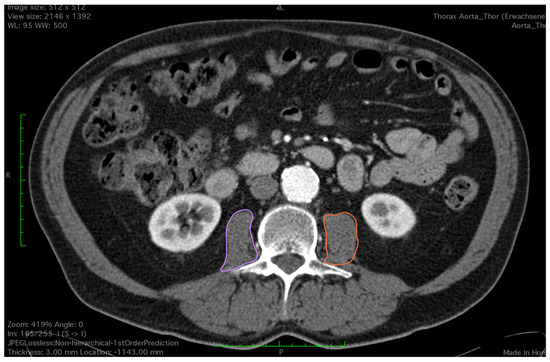

2.2. Assessment of Skeletal Muscle

- Mourtzakis, M.; Prado, C.; Lieffers, J.; Reinman, T.; McCargar, L.; Baracos, V.E. A practical and precise approach to quantification of body composition in cancer patients using computed tomography images acquired during routine care. Appl. Physiol. Nutr. Metab. 2008, 33, 997–1006. [Google Scholar] [CrossRef] [PubMed]

- Shen, W.; Punyanitya, M.; Wang, Z.; Gallagher, D.; St.-Onge, M.-P.; Albu, J.; Heymsfield, S.B.; Heshka, S. Total body skeletal muscle and adipose tissue volumes: Estimation from a single abdominal cross-sectional image. J. Appl. Phsyiol. 2004, 97, 2333–2338. [Google Scholar] [CrossRef] [PubMed]